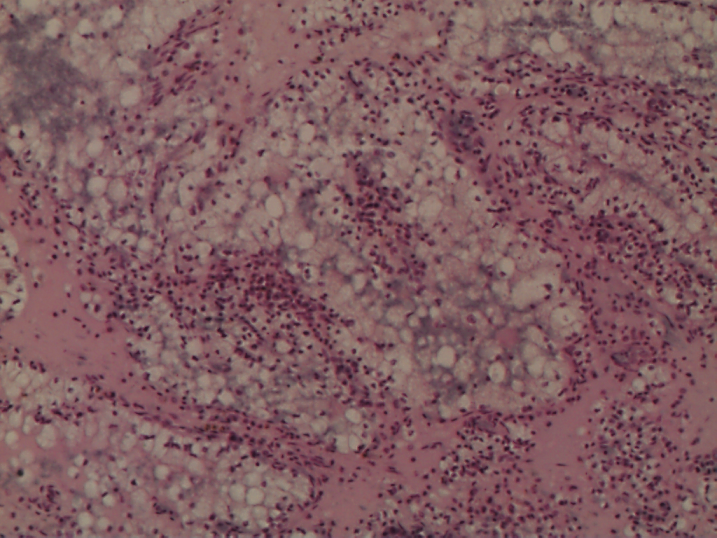

225. Фолликулярный пиелонефрит

В почке выражено разрастание зрелой соединительной ткани с инфильтрацией лимфоцитами и единичными нейтрофилами. Много лимфатических фолликулов со светлыми «зародышевыми центрами». Канальцы атрофичные. Часть канальцев резко растянут эпителий их уплощен, в просвете — белковые цилиндры. Отмечается склероз отдельных клубочков, стенок артерий и вен.

Существенные элементы: 1. разросшаяся соединительная ткань

2. лимфатические фолликулы

3. атрофичные канальцы

4. склероз и гиалиноз клубочков

5. регенерационная гипертрофия нефронов

6. лимфоплазмоцитарные и нейтрофильные инфильтраты

4

3

1

6

2